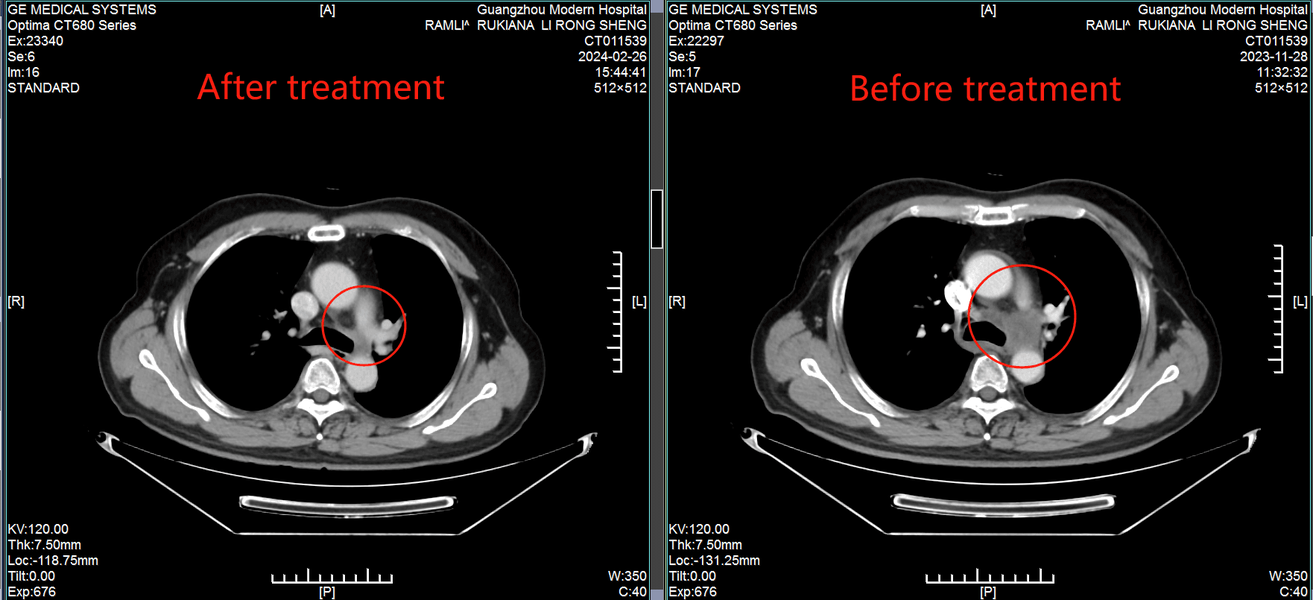

История пациента: Лоррейн, 61 год, Австралия. Диагноз: Плоскоклеточный рак молочной железы (T4N2M1), поздняя стадия с изъязвлением и кровотечением. Тактика лечения: Эмболизация опухолевых сосудов и внутриартериальная химиотерапия. Результат: После двух процедур достигнута регрессия опухоли на 60%, восстановлена мобильность и улучшено качество жизни.

Результат, вернувший веру Эффект от лечения превзошел ожидания.

После двух процедур опухоль уменьшилась на 60%, что позволило остановить кровотечение и значительно улучшить самочувствие Лоррейн. Она не только встала на ноги, но и вернула себе самостоятельность.

«Я счастлива, что настояла на своем. Здесь мне не только подарили шанс на жизнь, но и подробно объяснили каждый шаг лечения. Персонал невероятно внимателен и профессионален. Я хочу верить в полное выздоровление и надеюсь, что моя история придаст сил другим пациентам не сдаваться и искать возможности», - говорит Лоррейн. Контрольное обследование в апреле 2025 года подтвердило стойкую положительную динамику. История Лоррейн - это пример того, как вера в современную медицину и готовность к решительным шагам способны победить даже самый сложный диагноз.